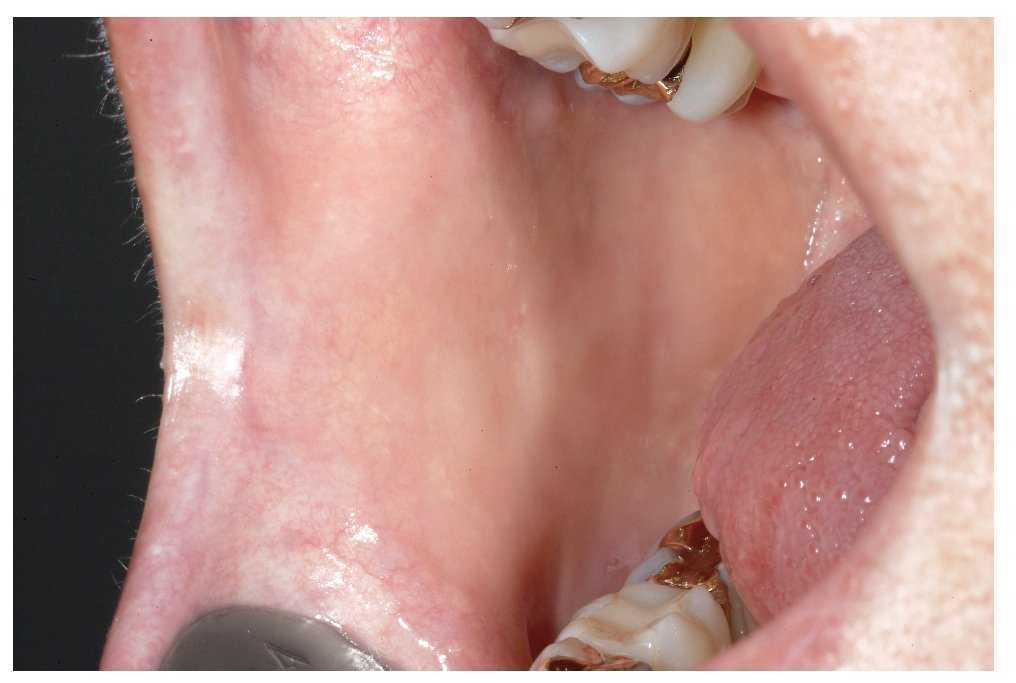

Para la inspección intraoral propiamente dicha hacen falta dos espejos bucales. Se ha demostrado la eficacia del procedimiento siguiente: en primer lugar se explora la mucosa yugal del lado derecho y a continuación el borde del vestíbulo y la mucosa alveolar vestibular del maxilar, empezando por la región del 18. A continuación, se procede con la inspección de la mucosa yugal del lado izquierdo, empezando por la comisura labial hasta las amígdalas (figs. 3 a 6). La exploración sigue con la inspección del borde del vestíbulo inferior hasta la zona del tercer molar inferior derecho y de la mucosa yugal del lado derecho.

Figura 6. Aspecto de la mucosa yugal en el lado izquierdo.